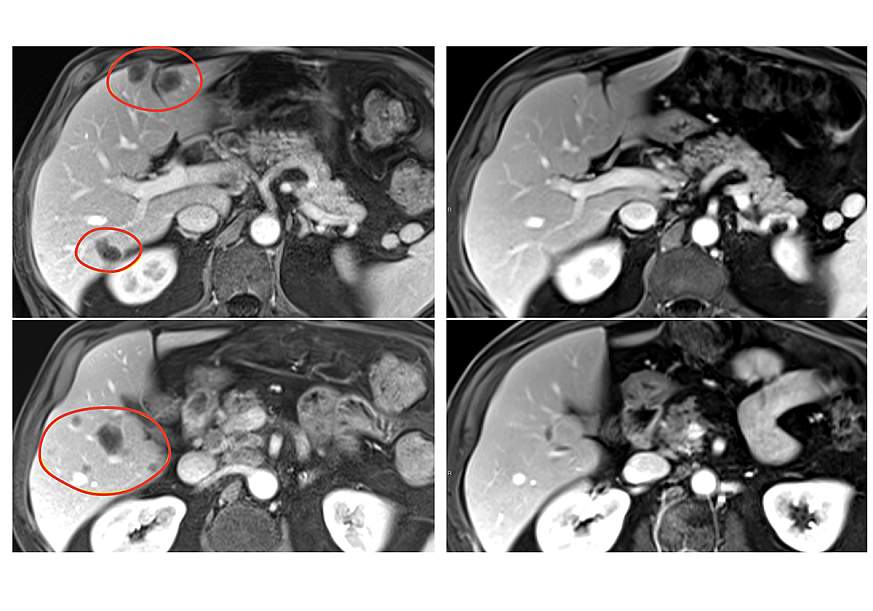

Combination immunotherapy shrank a variety of metastatic gastrointestinal cancers

A new form of tumor infiltrating lymphocyte (TIL) therapy, a form of personalized cancer immunotherapy, dramatically improved the treatment’s effectiveness in patients with metastatic gastrointestinal cancers, according to results of a clinical trial led by researchers at the National Institutes of Health (NIH). The findings, published April 1, 2025 in Nature Medicine, offer hope that this therapy could be used to treat a variety of solid tumors, which has so far eluded researchers developing cell-based therapies.

Patients in the clinical trial, who had a variety of gastrointestinal tumors, also received the immune checkpoint inhibitor pembrolizumab (Keytruda) to help further boost their immune response. The result was nearly 24% of patients treated with selected TILs plus pembrolizumab had a substantial reduction in the size of their tumors, compared with 7.7% of patients who received selected TILs without pembrolizumab. Patients treated with TILs that had not been selected for anti-tumor activity had no tumor shrinkage.

The clinical trial included 91 patients with metastatic gastrointestinal cancers—including esophageal, stomach, pancreatic, colon, and rectal cancers—that had worsened despite a median of four prior treatment regimens. In the pilot phase of the trial, 18 patients were treated with TILs that had not been selected for anti-tumor activity, and there were no objective responses (tumor shrinkage of at least 30% is considered an objective response). In the second phase, 39 patients were treated with selected TIL therapy, and three (7.7%) had objective responses.

In the third phase, 34 patients received pembrolizumab immediately before selected TIL therapy to prevent the newly introduced immune cells from becoming inactivated by the patient’s own immune system. This group had the best response, with 8 of 34 (23.5%) patients experiencing an objective response. All 91 patients had also received standard chemotherapy and high-dose interleukin-2 before the TIL therapy.

In the trial’s second and third phases, objective responses were seen in multiple types of gastrointestinal cancers, including cancers of the colon, rectum, pancreas, and bile duct. Responses lasted between 8 months and more than 5.8 years in the group that received selected TIL therapy alone, and between 4 months and 3.5 years in the group that received selected TIL therapy and pembrolizumab. Serious side effects occurred in 30% of patients treated with selected TILs.